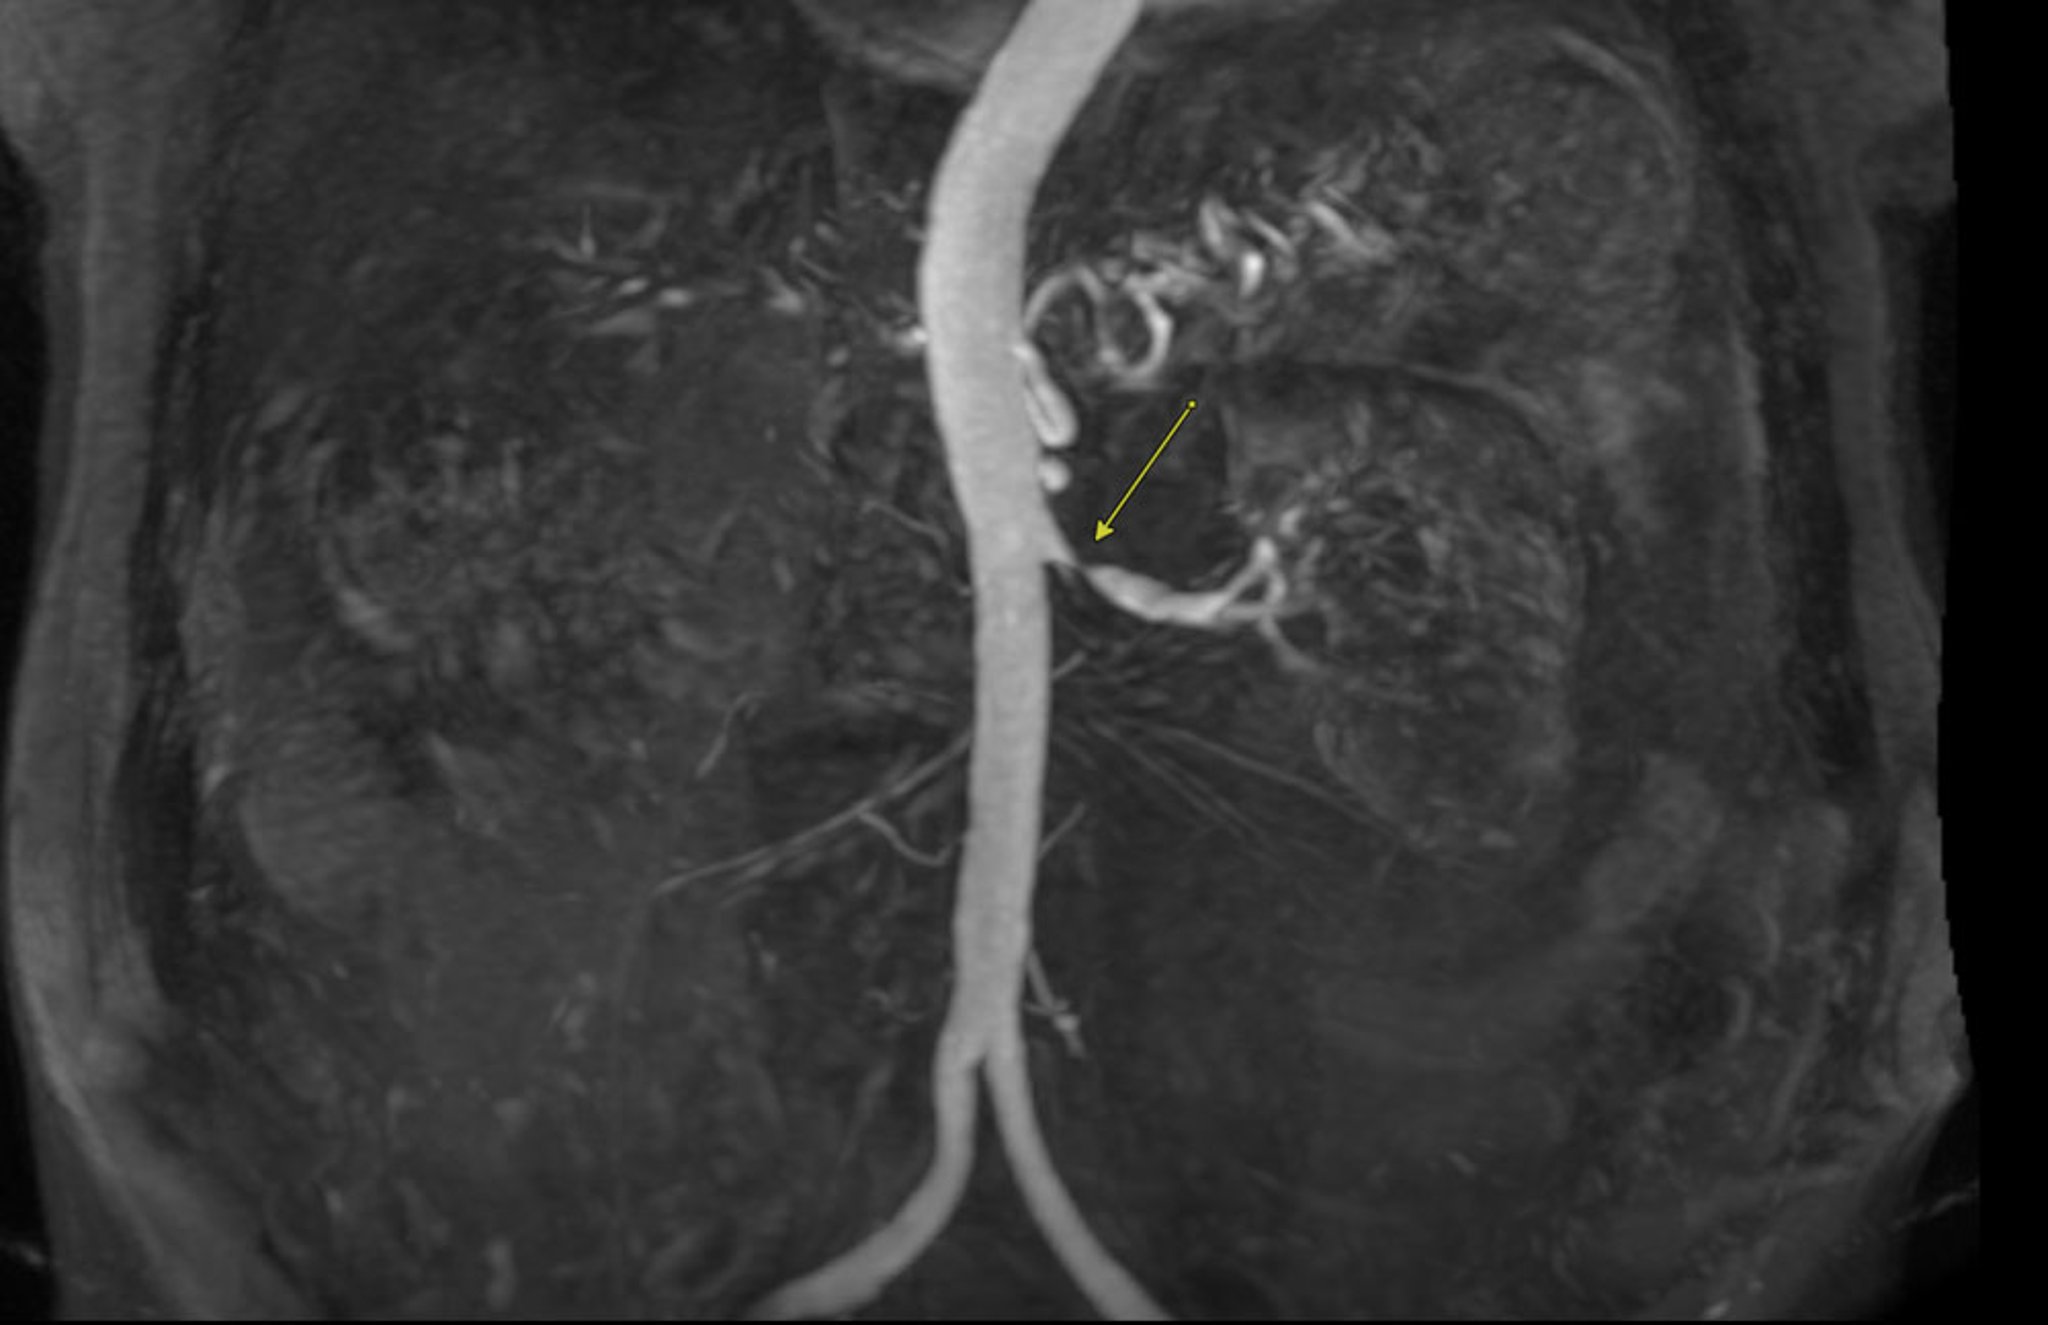

含钆基对比剂的磁共振血管成像(MRA)

此增强磁共振血管成像显示严重的肾动脉狭窄(箭头所示)。

Image courtesy of Attila Feher, MD, PhD.